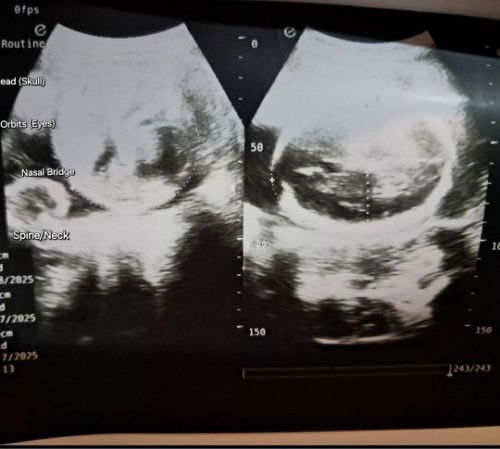

Hello mga momshie ask ko lang sana kung nakakalaki ba ng baby yung laging pag tulog?? lagi na kase ako inaantok tas pag gising ko kikilos naman ako ng kikilos .. sabi kasi ng sister in law ko lalaki daw si baby pag tulog ng tulog baka mauwi daw ako sa cs totoo po ba na lumalaki si baby pag lagi kang tulog ng tulog at di nag kikikilos ???? #7MonthsPreggyBumpWithMyBabyGirl